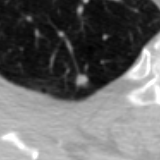

The current study focuses on lung nodule retrieval from a database of CT scans, where patches taken from CT slices of pulmonary nodules are to be mapped into an embedding. LIDC-IDRI [5] is a dataset of thoracic CT scans of 1,010 patients. All the scans were annotated by up to four radiologists, where each one identified, segmented and evaluated separately the lung nodules of a diameter above . Their evaluation also included ratings for a set of 9 characteristics: Subtlety, Internal structure, Calcification, Sphericity, Margin, Lobulation, Spiculation, Texture and Malignancy. The rating system was based on a discrete score of 1-5. Four examples of nodule patches are illustrated in Figure 2: 2 benign (a, b) and 2 malignant (c, d). A rounded vector of the mean rating is bellow each nodule, with the characteristics ordered according to the listing above. The most prominent difference between a and b is the calcification: 3 (solid) and 6 (absent) accordingly. d compared to c has a more defined margin, is more lobulated, but less spiculated. The malignancy score is used to define malignancy classes: score of 1-2 is benign, score of 3 is unknown, and a score of 4-5 is malignant.

(a) Benign

3, 1, 3, 3, 4, 3, 1, 5, 1

(b) Benign

3, 1, 6, 5, 5, 1, 1, 5, 2

(c) Malignant

5, 1, 6, 3, 3, 4, 1, 5, 5

(d) Malignant

4, 1, 6, 3, 4, 2, 2, 5, 4